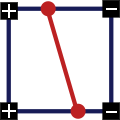

2. Два квадрата одного знака и два противоположного, причем квадраты с одинаковым знаком находятся по одну сторону, движение контура идет вертикально или горизонтально:

Конкретно первый и второй случаи: